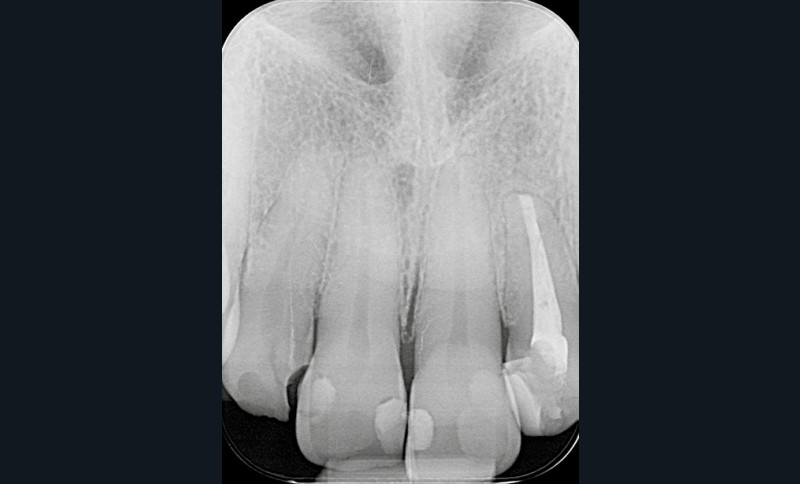

- un retraitement orthograde présente un mauvais rapport bénéfice-risque : par exemple, la présence d’un tenon dont la dépose pourrait fracturer la dent (fig. 2a-b) ;